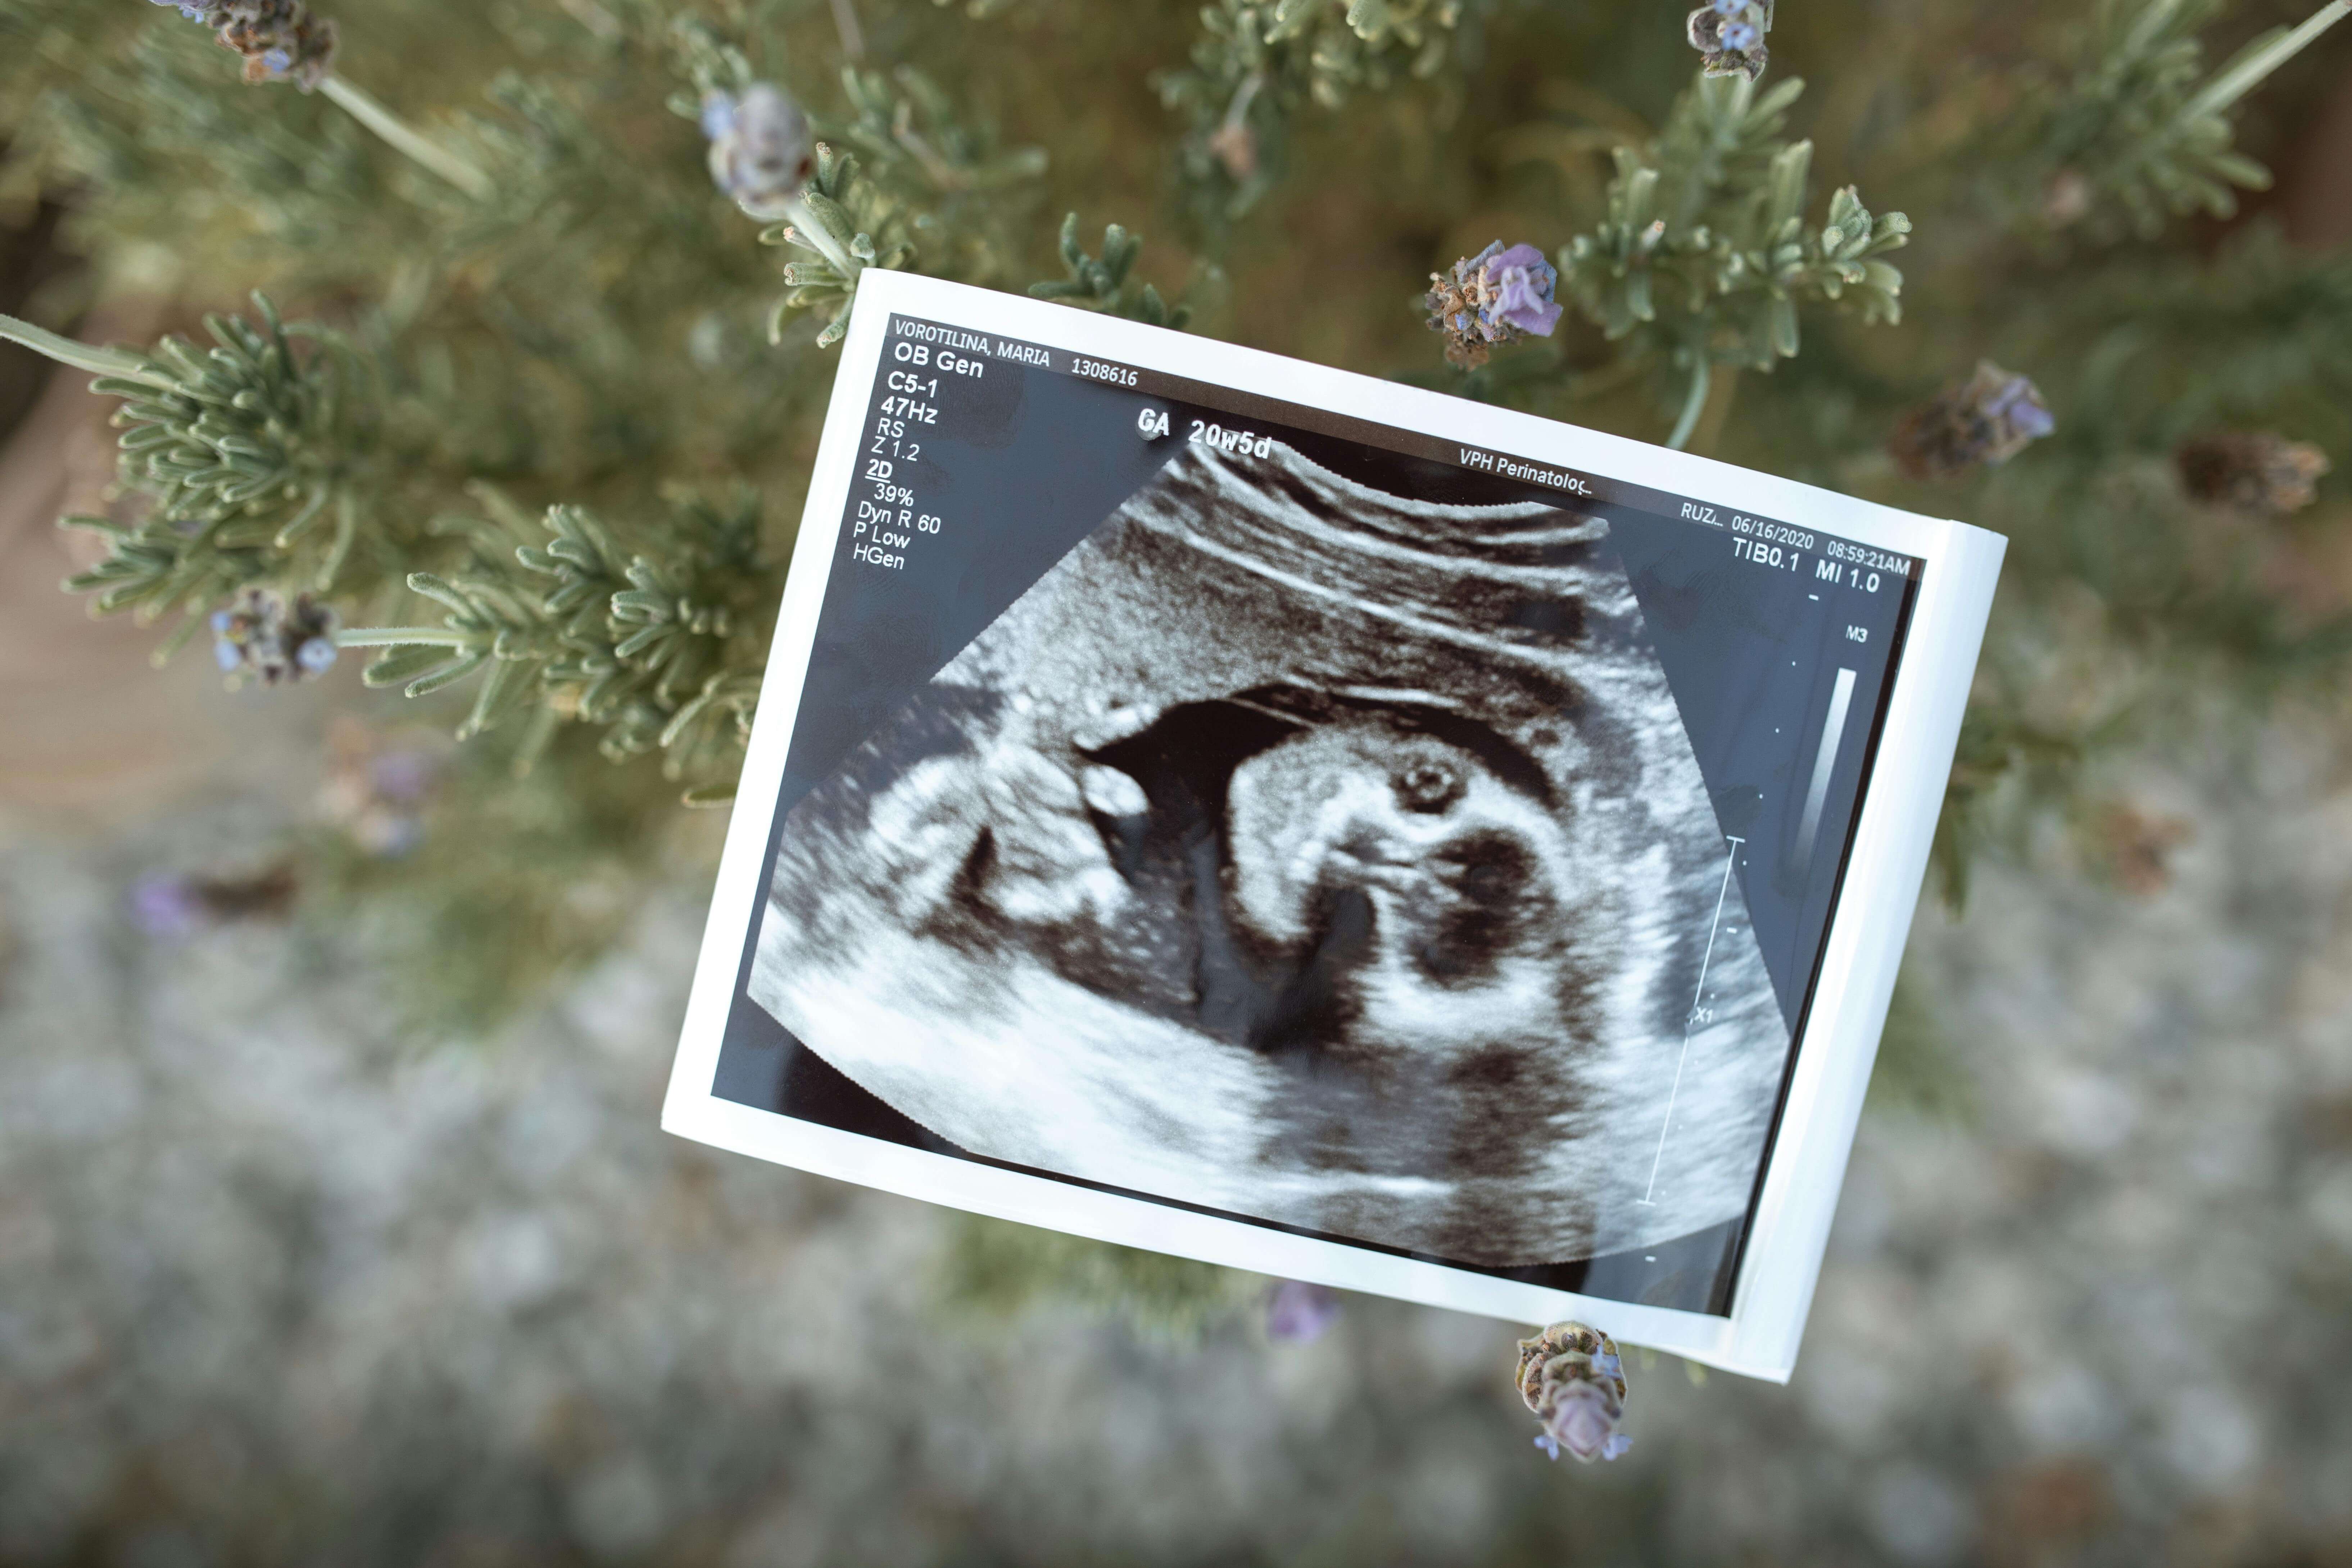

건강한 임신과 출산을 준비하기 위해서는 사전에 자신의 건강 상태를 점검하는 것이 매우 중요합니다. 특히 임신을 계획하고 있는 여성이라면 여자 산전검사 항목을 숙지하고, 필요하다면 보건소에서 제공하는 무료 산전검사도 적극 활용하는 것이 좋습니다. 이번 글에서는 여자 산전검사 항목과 함께 보건소 산전검사 항목까지 자세히 정리해드립니다.

여성의 건강 상태는 임신의 성공 여부는 물론 태아의 성장과도 밀접한 관계가 있습니다. 감염 여부, 만성 질환, 유전 질환 유무 등을 미리 확인하고 적절한 대처를 한다면, 보다 안전하고 건강한 임신이 가능합니다. 특히 여자 산전검사 항목은 초기 임신에 영향을 줄 수 있는 요인을 미리 파악하는 데 초점이 맞춰져 있습니다.